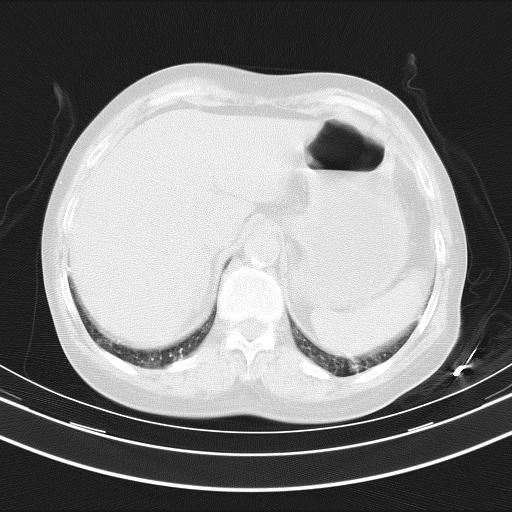

1)两肺感染性病变;建议抗炎治疗后复查。2)纵隔淋巴结肿大。3)左侧胸腔积液。

2)纵隔淋巴结肿大。

3)左侧胸腔积液。